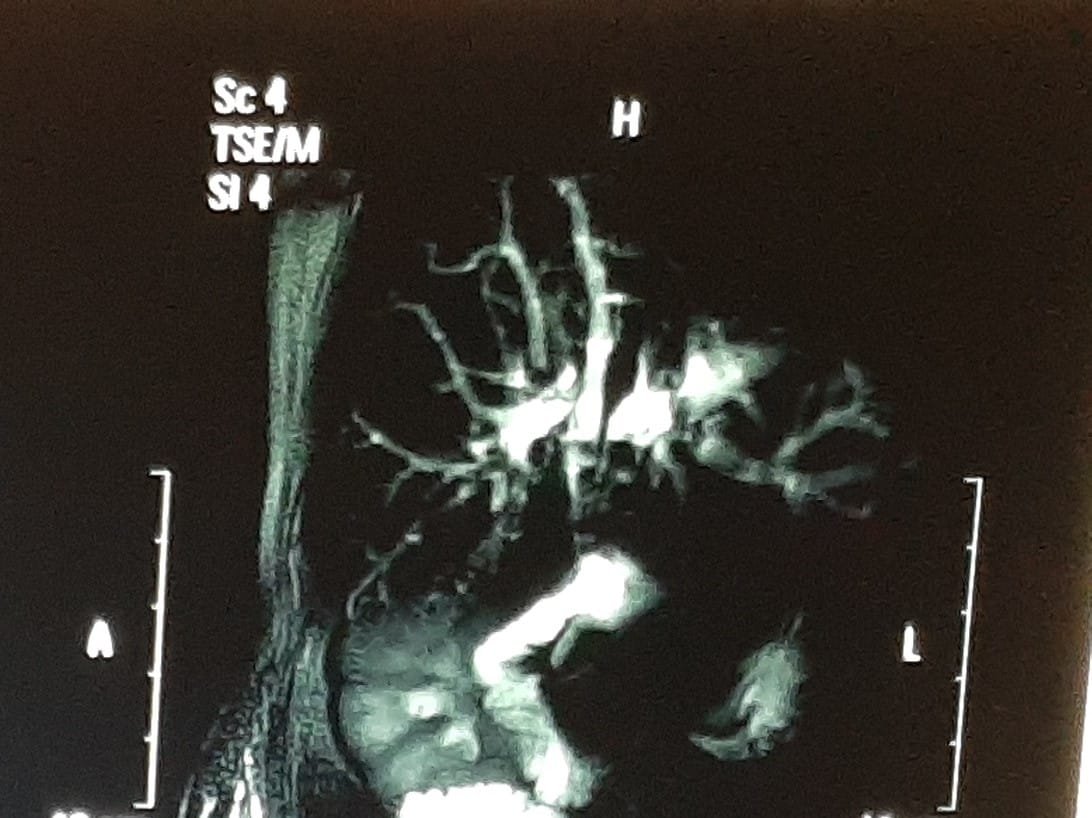

Section bile duct surgery, picture: mri showing stone reappeared after 15 years of bile duct surgery for stones

Above patient...a redo surgery performed for recurrent bile duct stones.. A completed hepaticojejunostomy anastomosis after clearings stones.